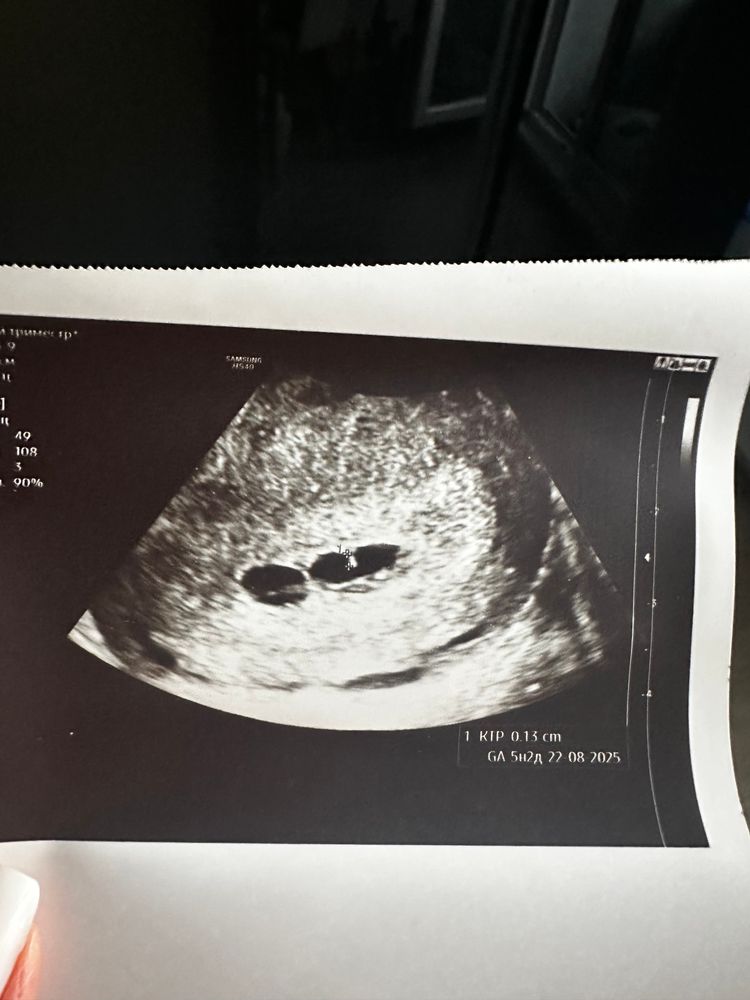

В субботу на узи сказали,что под вопросом двойня,два плодных яйца 4,4 и 3,9(для такого срока 6+3 же супер мало)или что-то непонятное,в воскресенье в другом месте сказали,что замершая и вообще все плохо,шансов нет,но поинтересовались,не было ли двойни в роду.

По фото очень похоже на двойню, причём тут вообще замершая, следите за динамикой хгч , растет значит все хорошо , и сходите совсем к другому узисту, а нервничать не стоит только хуже себе сделаете

Но по УЗИ - очень на двойню похоже, просто не пойму, с чего на замершую подумали. Смотрите просто в динамике, если растут - нормально все, живые растущие ляльки

Анна, пусть так и будет🙏Замершую подозревают по плодным яйцам,деформированы сказали,плюс на таком сроке вроде как жм должен быть да и эмбрион да и сердцебиение🙈Шла на узи в полной уверенности,что вот сейчас услышу сердечко🥺